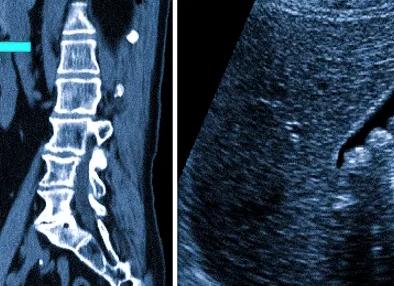

После диагностики заболеваний органов или изменений в области малого таза с помощью УЗИ, иногда назначают МРТ. Возникает вопрос: Неужели УЗИ не справилось с задачей, или методика МРТ малого таза дает дополнительные возможности для изучения органов и структур?